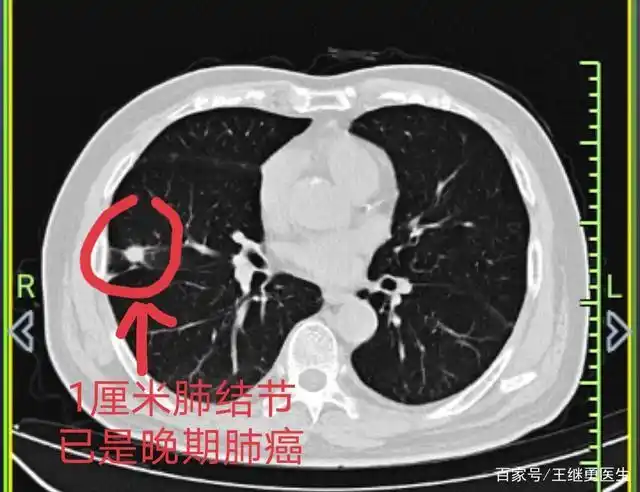

年年做胸部ct,为什么还会得晚期肺癌!